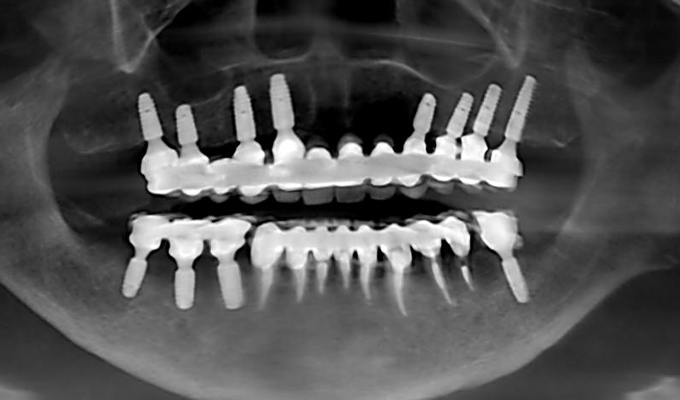

最新メンテナンス時(2023年)

- 上・・・虫歯の根だけの歯が数本残っているためすべて抜歯し仮義歯作成しました。最終的には8本インプラントを埋入し上部構造はメタルボンドです。

下・・・保存できる下の歯はメタルボンドブリッジにし、奥歯のない部分に3本インプラントを埋入しました。治療期間は2年ほどかかりましたがしっかり食事ができるようになったので嬉しいと、満足していただけました。

以降定期的にメンテナンスに来院いただき11年経過してもいい状態を維持されています。